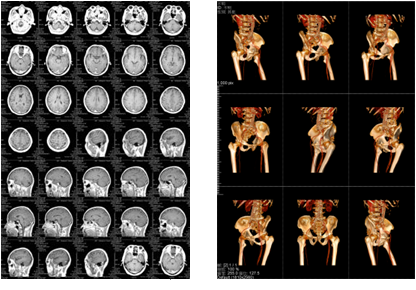

醫療行業辦公解決方案|柯尼卡美能達復印機彩色影像輸出新思路,成功實現了媲美膠印的輸出效果,并且顯著降低輸出的單張成本,更一舉解決了節省主機采購成本、綠色環保、設備維護等諸多問題。辦公解決方案定制熱線:4000-600-993!

由于醫療行業影印技術和耗材的特殊性,該行業放射科影像輸出長期以來都被少數膠片打印機廠商所壟斷:放射科的影像通常以DICOM的格式進行保存(普通輸出設備不支持該格式),輸出也只能采用價格昂貴的傳統膠片打印機和干式膠片,由此導致醫療單位放射科影像輸出存在著打印成本高、膠片視覺效果不好、膠片材質污染環境等諸多問題。

全球領先的商務解決方案增值服務商——柯尼卡美能達打破了上述局面,通過為河北省廊坊市某三甲醫院量身定制的彩色影像輸出解決方案為醫療行業彩色影像輸出開辟了全新思路,該方案通過利用DICOM轉換服務器,配合柯尼卡美能達旗下高效穩定的A3彩色數碼復合機bizhub C364e以及優質的膠片紙,成功實現了媲美膠印的輸出效果,并且顯著降低輸出的單張成本,更一舉解決了節省主機采購成本、綠色環保、設備維護等諸多問題。

成本優化兼具環保一舉兩得

該三甲醫院放射科負責日常CT、核磁共振影像的輸出,平均的日打印量在1000張左右。在導入解決方案前,該放射科的影像輸出使用干式膠片打印傳統膠片,輸出設備價格不菲,而且傳統膠片價格更是高昂。另外,傳統膠片不能實現彩色輸出,醫生必須在背光板上進行診斷,膠片本身還含有重金屬等有毒物質,污染環境。為此,柯尼卡美能達向專業供應商采購了DICOM轉換服務器和符合醫院要求的打印膠片紙,可實現三維打印,打印的影像可直接在自然光下觀看,便于醫生診斷;膠片紙的成本是傳統膠片的三分之一而且不含毒物質,既節省成本又綠色環保。

膠片紙輸出樣張示意--科頤辦公分享

膠片紙輸出樣張示意